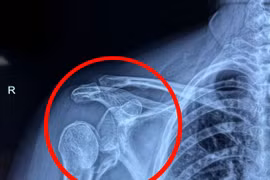

Phần xương ở đầu trên cánh tay đã gãy nát nếu bảo tồn thể dẫn đến hoại tử chỏm xương và ổ chảo cánh tay, đau đớn kéo dài và mất khả năng vận động. Thay khớp vai nhân tạo đảo nghịch là giải pháp hữu hiệu.